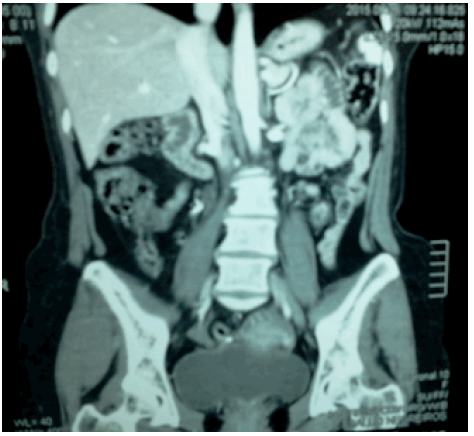

La Figura 1 corresponde a una TAC de abdomen con contraste, vesícula biliar no visible e hígado morfológicamente conservado, con presencia de imágenes de aspecto quístico subcentimétrico dispersos en el parénquima hepático, no se observan adenopatías retroperitoneales.